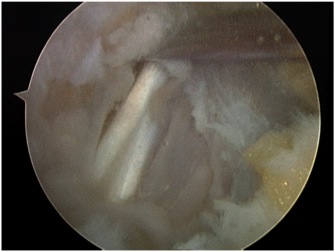

Arthroscopic FHL release and os trigonum excision

Technique

Vumedi arthroscopic os trigonum resection 1

Vumedi arthroscopic os trigonum resection 2

FHL exposure in posterior ankle arthroscopy